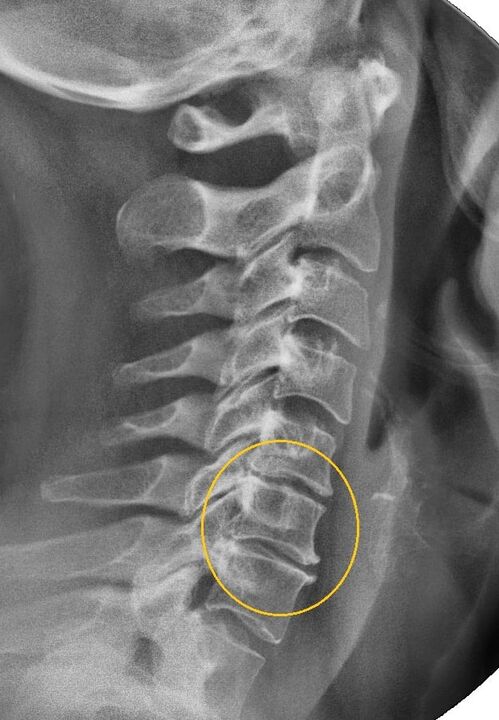

Най-информативната диагностична процедура е радиографията. Патологиите от 1-ва степен съответстват на 1-ви или 2-ри рентгенологичен стадий. Получените изображения визуализират типичните признаци на заболяването.

| Рентгенови етапи на цервикална остеохондроза от 1 степен | Характерни признаци |

|---|---|

| Етап 1 | Незначителни промени в изкривяването на гръбначния стълб в цервикалната област, засягащи един или повече сегменти |

| Етап 2 | Леко удебеляване на междупрешленните дискове, деформация на гръбначните израстъци, изправяне на лордоза, незначителни израстъци на костни структури |